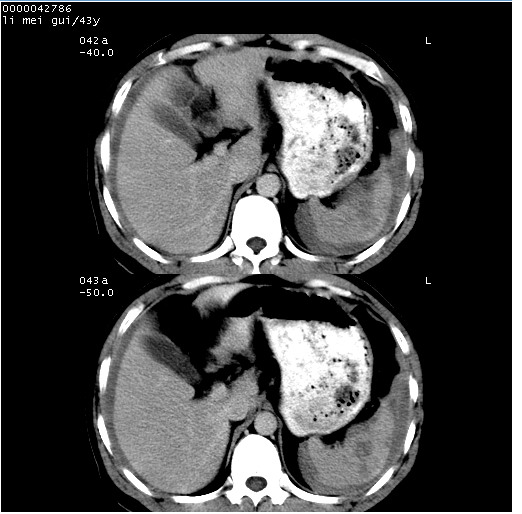

| 患者,男,43岁。突发腹痛2小时,面色苍白,难以平卧。自述近期无明确外伤史,为摩托车驾驶员。 腹部b超检查:脾脏中上极回声异常,肿瘤待排。 临床诊断:腹痛原因待查。 上中腹部ct轴位平扫+增强扫描(层厚10mm,螺距1.0,重建间隔10mm),图像如下: ![]() ![]() ![]() ![]() ![]() ![]() ![]() ![]() ![]() ![]() ![]() ![]() ![]() ![]() ![]() ![]() ![]() ![]() ![]() ![]() ![]() ![]() ![]() ![]() ![]() ![]() ![]() ![]() ![]() ![]() ![]() ![]() ![]() ![]() ![]() zrs发言:支持脾破裂 wwp发言:支持脾破裂并腹水。 xulianj发言:脾脏肿瘤破裂可能性大 zsl6918发言:不像肿瘤出血,考虑还是与外伤后引起的慢性出血有关 zzyy发言:平扫见肝周及脾周积液,脾内密度不均。脾内肿瘤较少见。还是外伤性脾破裂。 沈丘东方医院发言:脾门区一个不均匀强化病灶与其周液体相连多考虑脾占位破裂出血 yixianman001011发言:脾破裂并腹水是可以肯定的,具体原因多以肿瘤性破裂出血,脾脏淋巴瘤可能性大. 结果: 术后,经详细询问患者,其仔细回忆:一月前骑摩托时左侧腰部与别人有“轻微”触碰,因责任在自已,当时又无明显不适,未引起注意。 临床术后诊断:脾破裂并失血性休克(1.外伤性迟发性脾破裂。2.脾脏肿瘤破裂?) 术后标本病检:脾破裂并出血,未见明显肿瘤成份。 原贴地址:http://www.radinet.com.cn/forum_view.asp?forum_id=4&view_id=34070 |